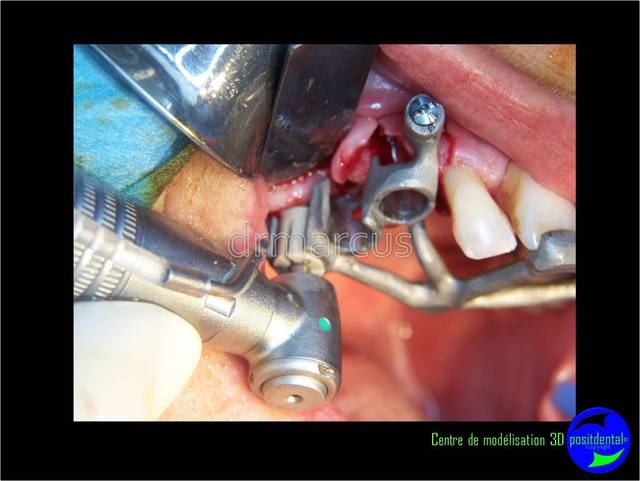

Analyse post-opératoire d’une MCI post-extractionnelle en chirurgie guidée

Cas clinique de drmarcus

Chirurgie : drmarcus

Dommage que ce soit scanner avant et Cone-Beam après. Il est vrai que l’interprétation peut différer. Toutefois on voit la parfaite superposition des implants entre la planification et la réalisation. J'en conclue que le système Positdental est relativement fiable ;-))))

Non sincèrement ce cas est en dehors des données acquises de la science mais sans Posit il était irréalisable.

J'apprécie tout particulièrement ma greffe in temporis.